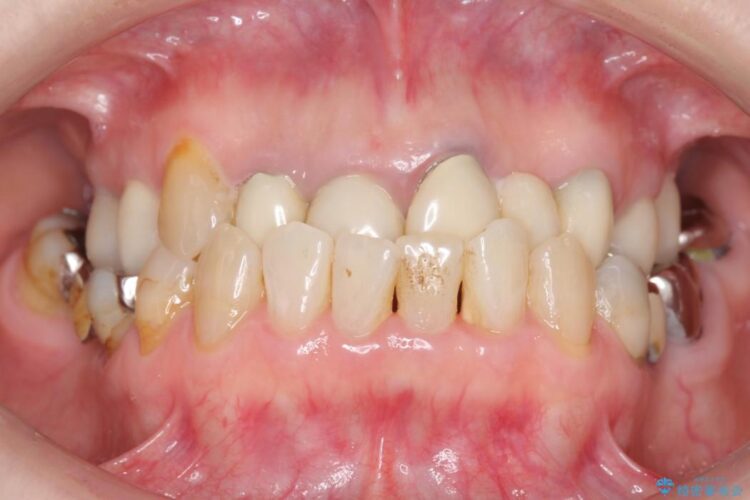

上顎右側の前歯2本のかぶせ物部分の再治療と犬歯に発生していた虫歯治療を主訴に来院されました。

前歯のかぶせ物に関しましては、内面が金属で覆われているため歯茎にその色が透けて見えるという審美的な問題と、かぶせ物と歯の境界が不適合であるという問題がありました。

犬歯の虫歯につきましては、何度も詰め物治療が繰り返されている痕跡があり今回虫歯を取りきるにあたり歯の強度に不安が残るため前歯と同時にかぶせ物の治療をしていくことを計画しました。